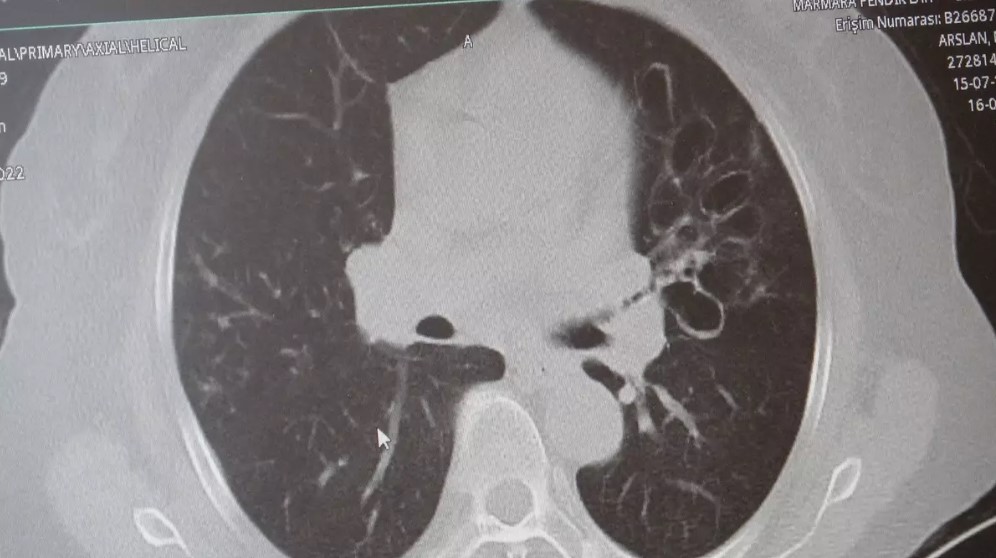

KOAH, akciğer dokusunun zamanla tahrip olmasıyla ortaya çıkıyor. Bu durum hastaları enfeksiyonlara karşı daha savunmasız hale getiriyor. Hastalık ilerledikçe nefes darlığı, kronik öksürük ve balgam artışı gibi belirtiler belirginleşiyor.

Uzmanlara göre zatürre ve bronşit belirtileri benzer olsa da hayati farklar bulunuyor. Bronşit, hava yollarının iltihaplanmasıyla sınırlıyken; zatürre, akciğerin en uç noktalarındaki alveolleri etkiliyor.